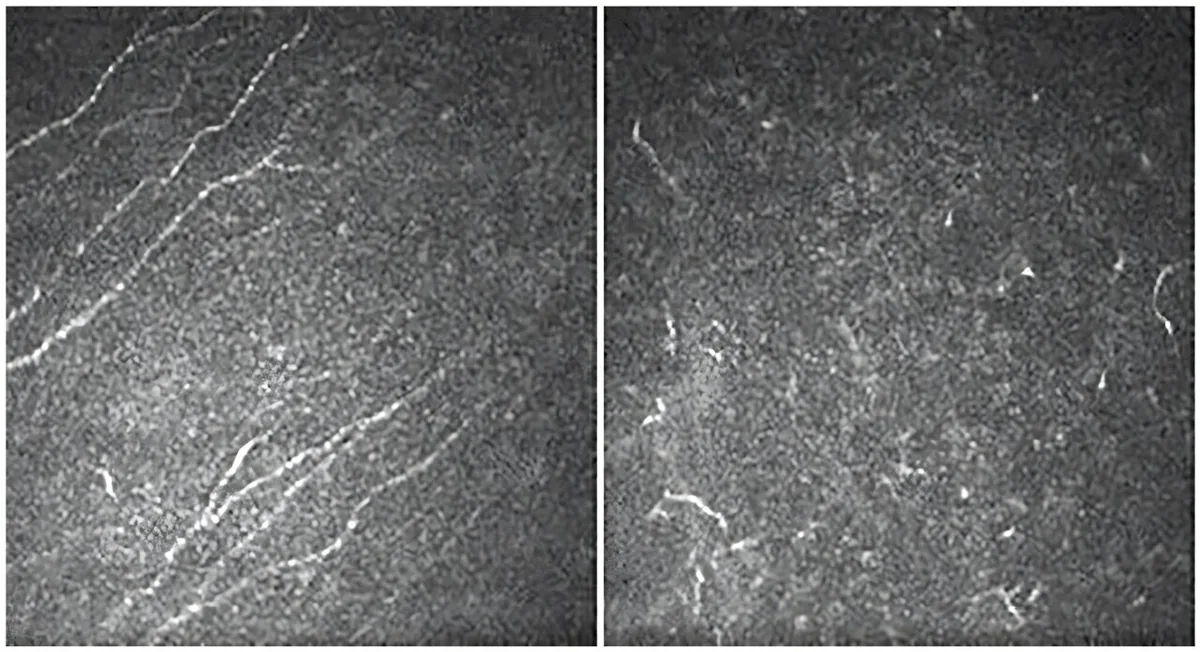

Clinical Study: Aniridia Triggers Progressive Corneal Sensitivity Loss